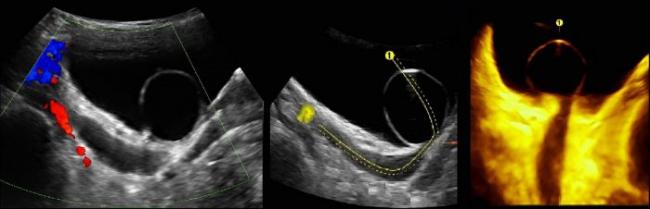

Уретероцеле на УЗИ

Исследование проводят при наполненном мочевом пузыре. Используют конвексный датчик 3,5-5 МГц. Смотри УЗИ мочевого пузыря (лекция на Диагностере).

На УЗИ в мочевом пузыре или в уретре определяется анэхогенное образование, округлой формы, с четким и ровным контуром; соответствующий мочеточник обычно заметно расширен; может присутствовать гидронефроз верхней части удвоенной почки. Уретероцеле определяют как внутрипузырные (полностью внутри мочевого пузыря) или внепузырные (некоторая часть постоянно расположена в шейке мочевого пузыря или в уретре).

Рисунок. Внутрипузырный (1) и внепузырный (2) уретероцеле.

Уретероцеле может варьировать в размерах от крошечной кистозной полости до большого баллона, который заполняет мочевой пузырь. Прогноз связан со степенью обструкции и рефлюкса. Важно измерить толщину и эхогенность почечной паренхимы, чтобы оценить степень повреждения почек.

Рисунок. Двустороннее уретероцеле на УЗИ: в режиме ЦДК из верхушек уретероцеле определяется выброс мочи.